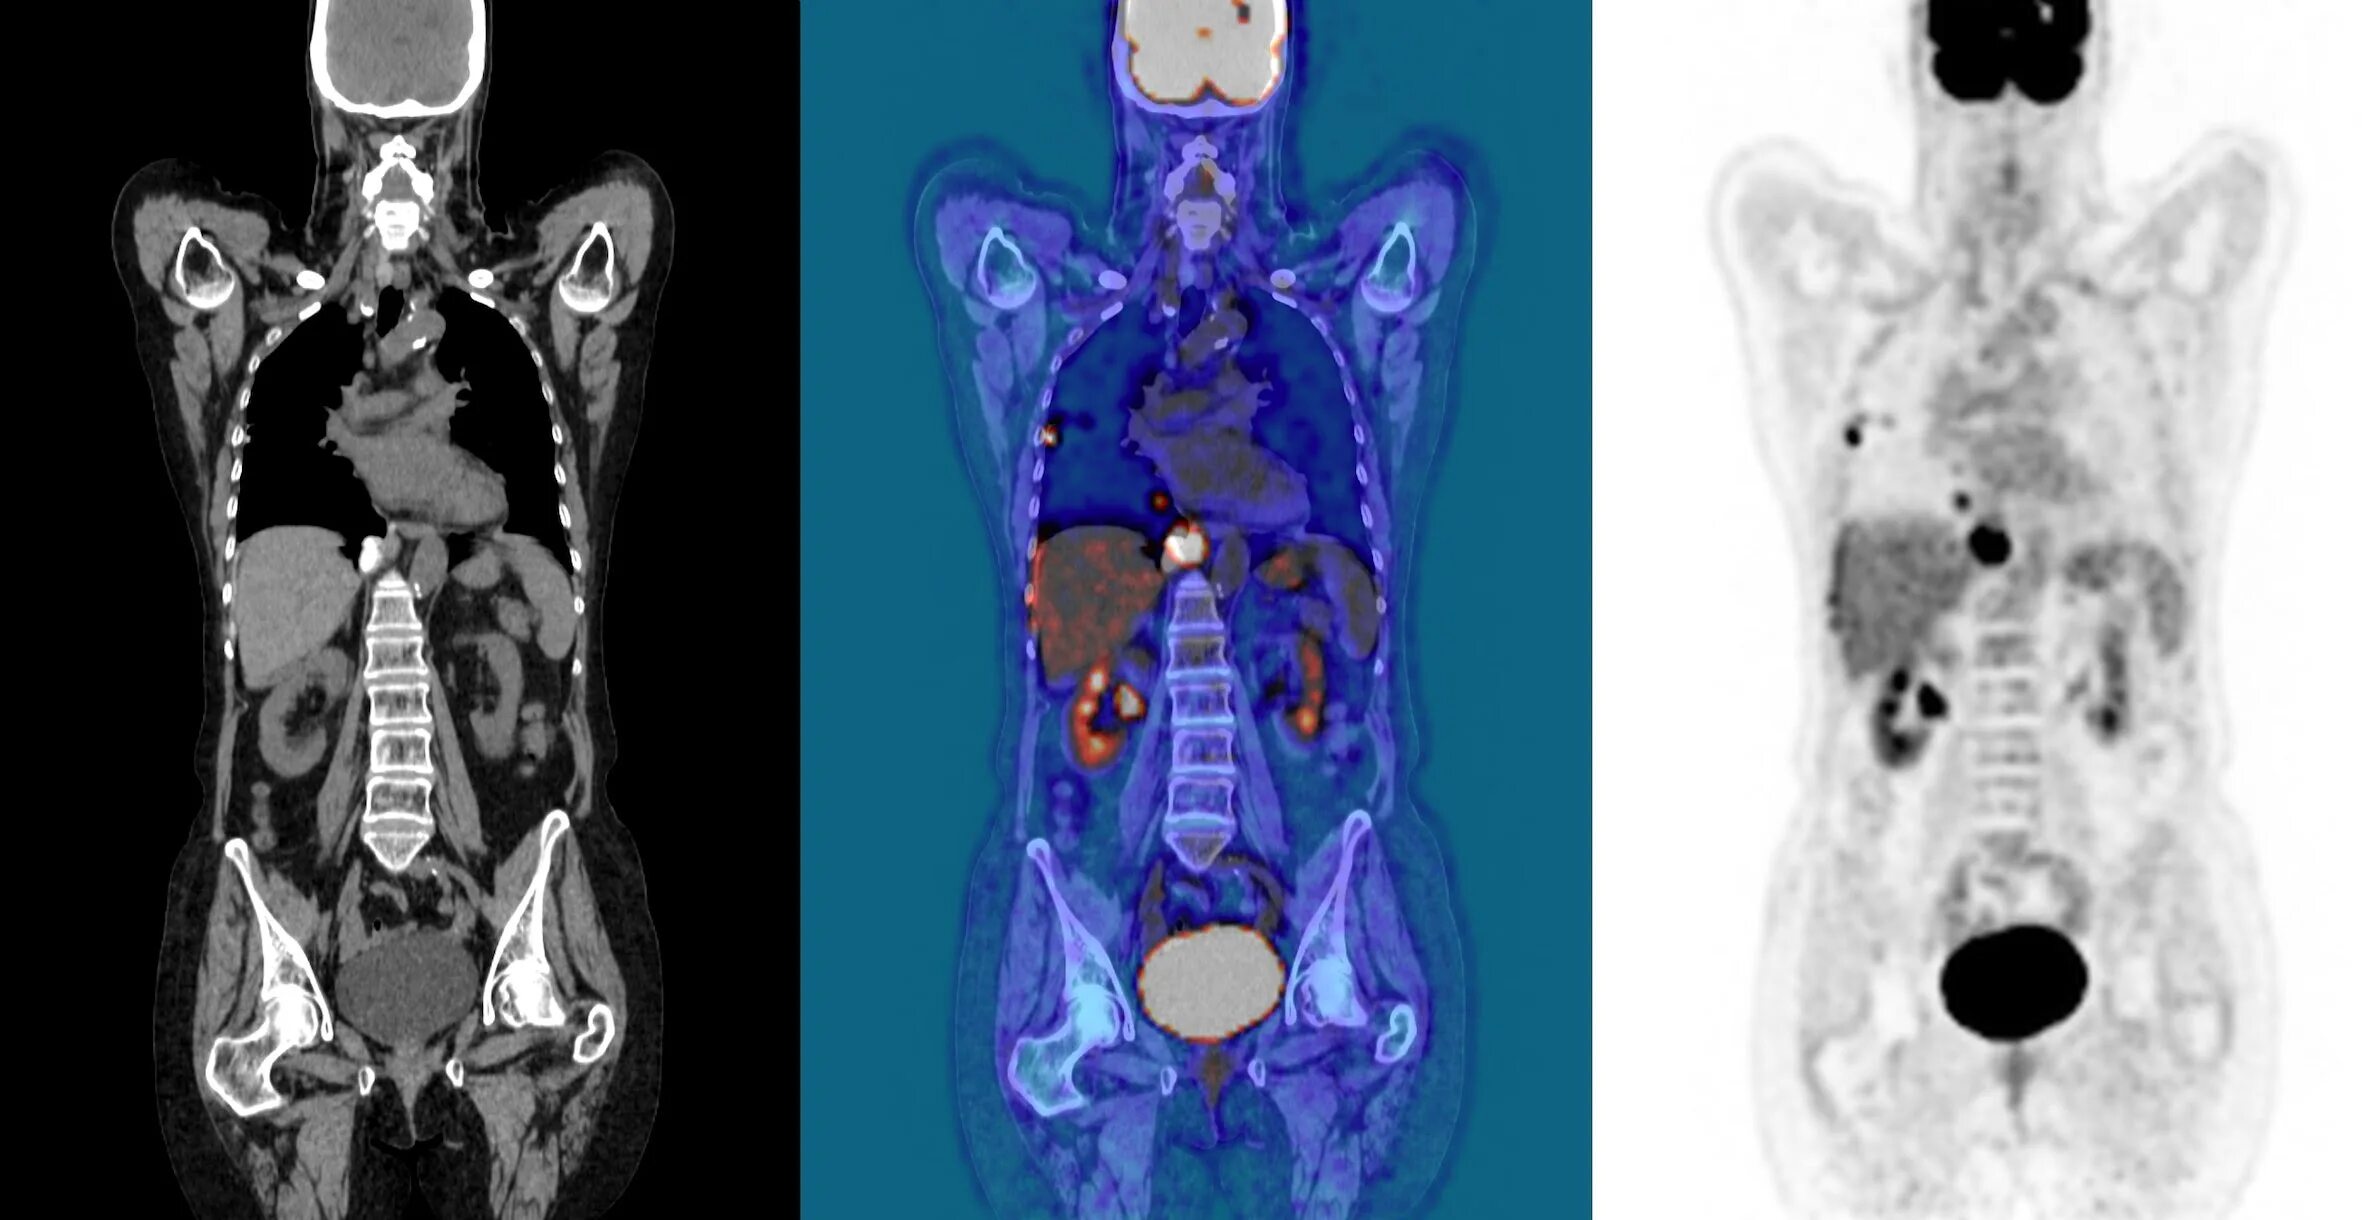

Пэт кт онкобольным